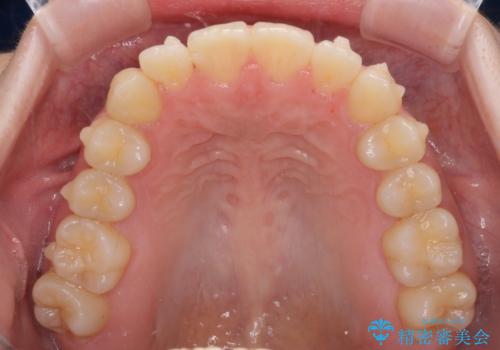

- ちょっとしたデコボコを整えたいとのことで来院された患者様です。

歯列不正は軽微であったため、インビザライン・ライトにより、費用を抑えて矯正治療を行うこととしました。

上下前歯の捻れが改善され、患者様には大変満足していただきました。